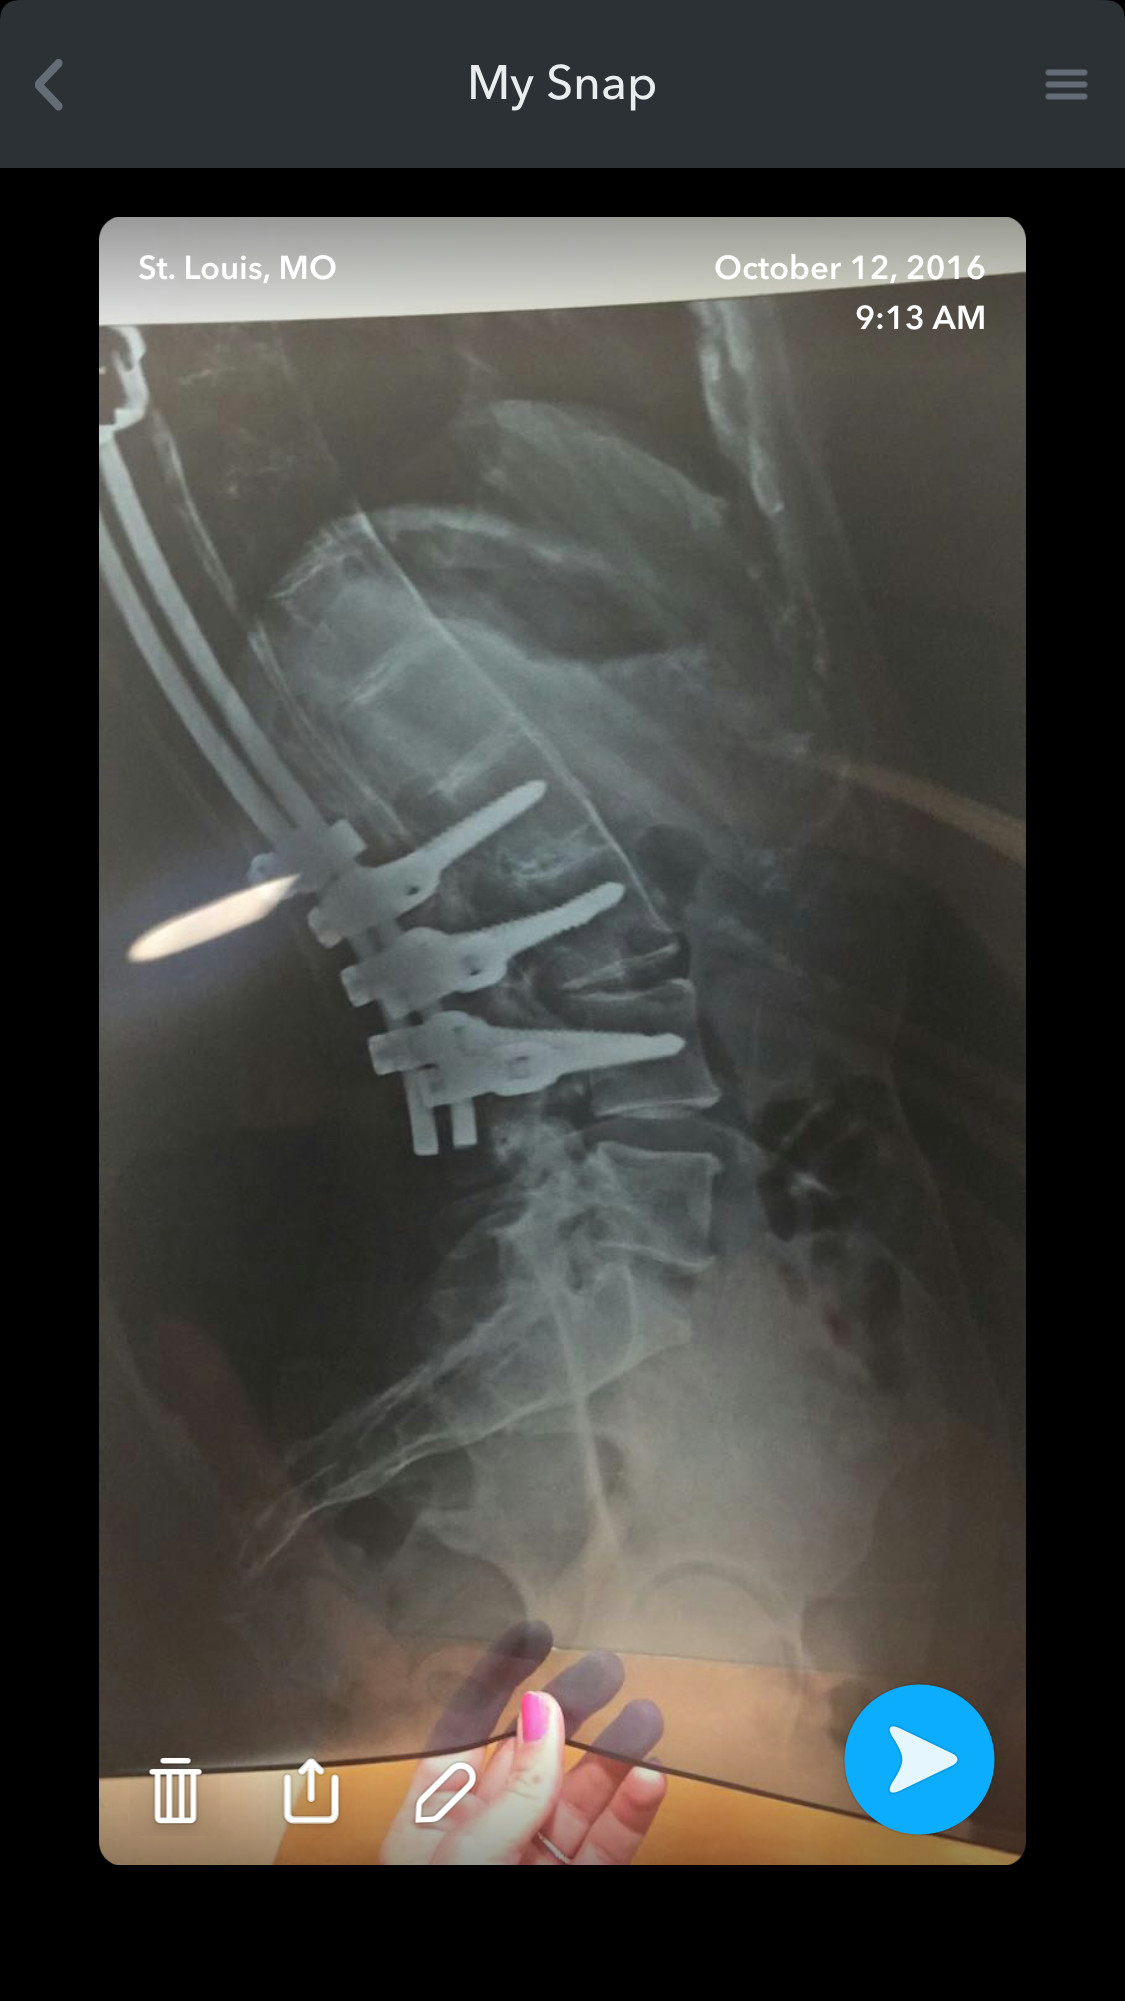

I'm Kristy. I was born with a benign spinal cord astrosytoma, a rare tumor that grew inside of my spinal cord. The doctor told my parents when they discovered the tumor that I had a better chance of winning the New York lottery than having the type of tumor in the location that I had it. I've had three tumor removal surgeries due to the tumor growing back several times and a lifetime supply of radiation treatment to kill it and prevent from growing any further. I've had 19 surgeries total, including rods inside my back, a spinal fusion for scoliosis, two leg lengthenings, and a foot reconstruction. Due to all of the surgeries and complications from the tumor, I was told I would never walk again. I've beaten the odds several times, and have learned to walk all over again starting from a wheelchair, to a walker, then to a cane and now just a full length KAFO leg brace. I am physically disabled on the left side of my body and walk with a limp.